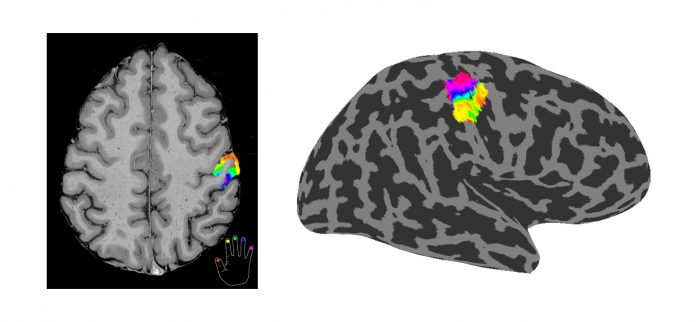

Here we use functional magnetic resonance imaging (fMRI), which enables the measurement of the increase in signal intensity in the part of the brain that is active in response to touch. However, because the changes in the signal intensities involved in touch are so small, it is difficult to use standard fMRI methods to map the changes that occur in response to touch with sufficient spatial resolution. For this reason, we use ultra-high field fMRI (UHF-fMRI) using a 7 Tesla MR scanner to form very high spatial resolution maps of the functional architecture of individual human brains.

Our group has previously used UHF-fMRI to form spatial maps of how individual fingers are mapped within the primary somatosensory cortex of the human brain, Figure 1, and the finer somatosensory sub-areas previously only defined by histology. We now plan to publish a probabilistic atlas of the representation of the fingers in the primary somatosensory cortex and to show how these sensory maps are altered in the brains of patients with clinical conditions. We will also use ultra-high submillimetre spatial resolution fMRI to assess cortical microstructure and unravel the functional organisation of the cortex at the level of the six cortical layers to assess feed forward and feedback connectivity.